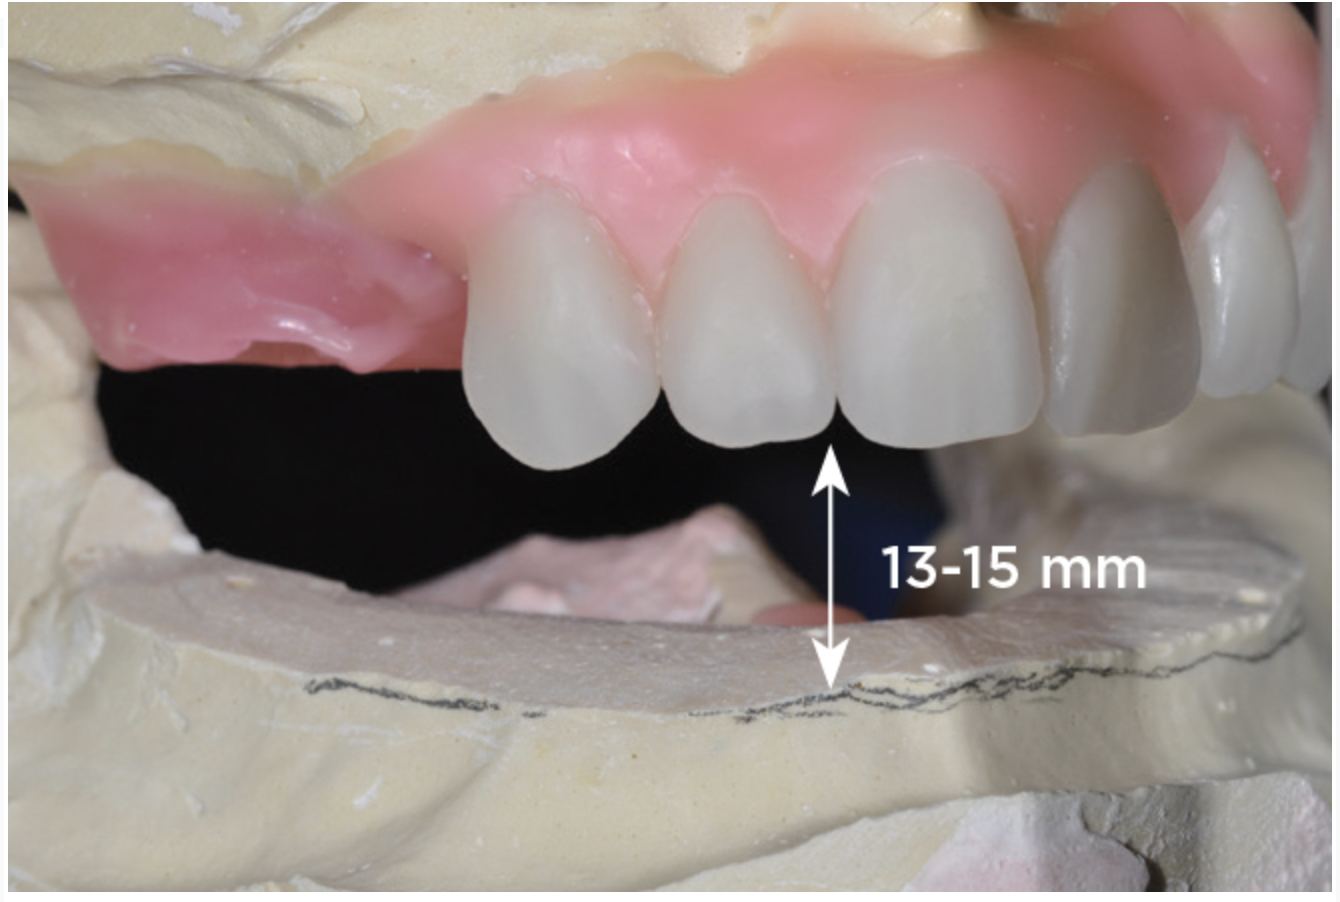

An important advantage of this approach is the ability to simulate bone reduction on the models and verify the presence of 15 mm to 17 mm and 13 mm to 15 mm of required inter-occlusal space for maxillary and mandibular restorations, respectively. This creates a platform for a diagnostic wax-up of the proposed dental rehabilitation and fabrication of wax prosthesis try-ins when necessary. Finally, a modified All-on-4 provisional prosthesis surgical and restorative guide developed by the authors for restoration-driven surgery and simplified restorative procedures is fabricated (Figure 2 through Figure 8).

Fig 4. Diagnostic wax-up performed after model surgery simulating maxillary tooth extraction. Note that inferior repositioning of the incisal plane helped create the 15 mm to 17 mm inter-occlusal space needed for the maxillary All-on-4 provisional restoration.

Figure 4

Fig 5. Bone reduction model surgery performed in mandibular arch to create 13 mm to 15 mm of inter-occlusal space required for the mandibular All-on-4 provisional restoration.

Figure 5